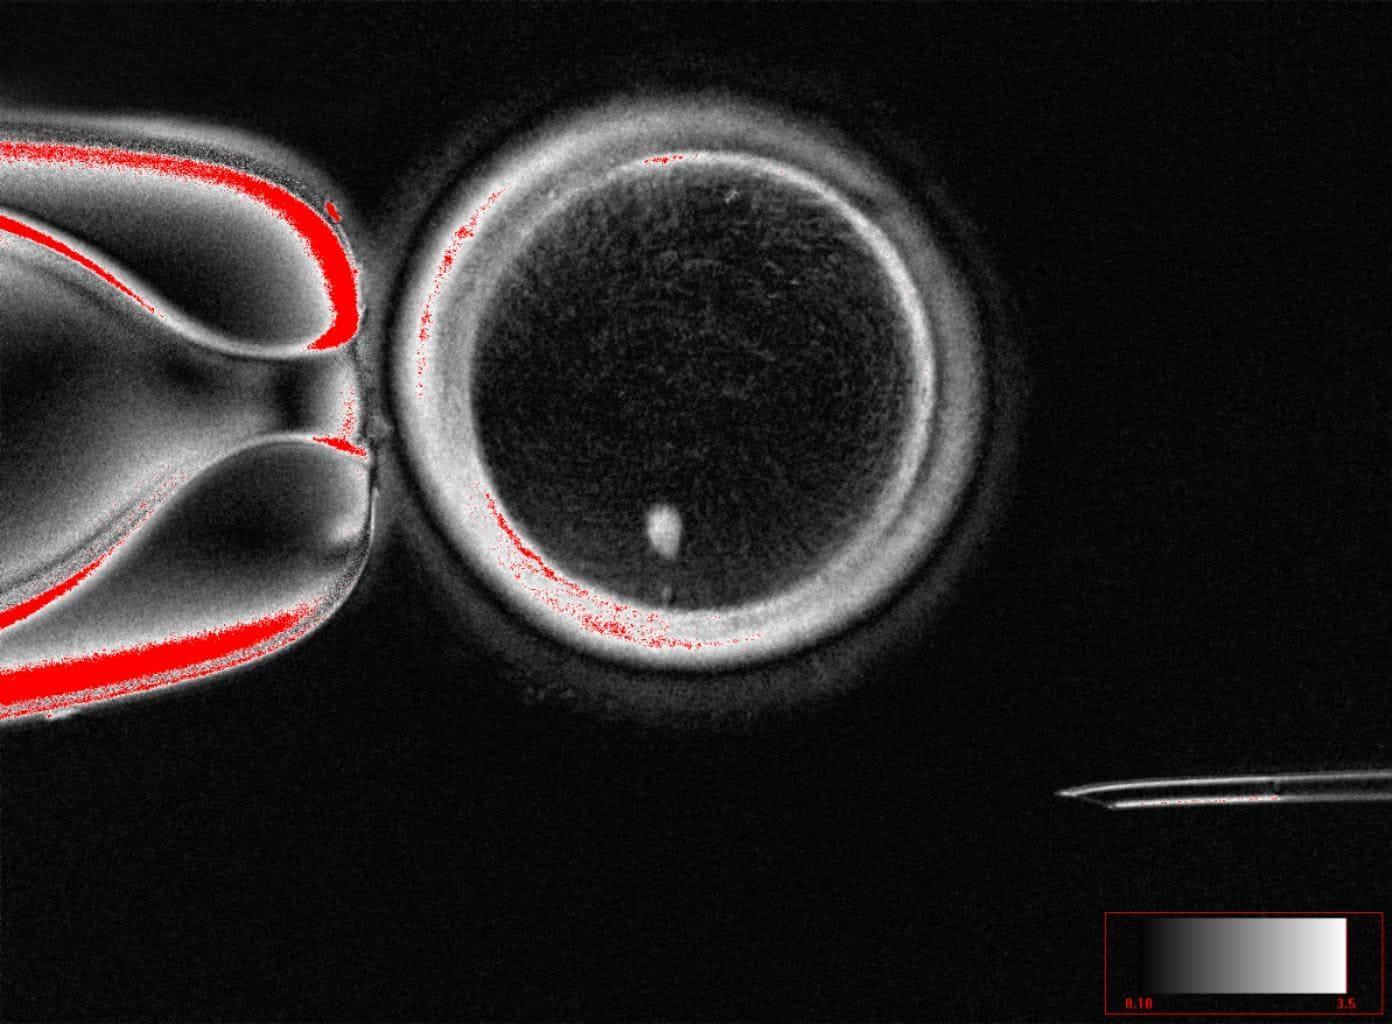

干細(xì)胞移植逆轉(zhuǎn)動(dòng)物中風(fēng)損傷